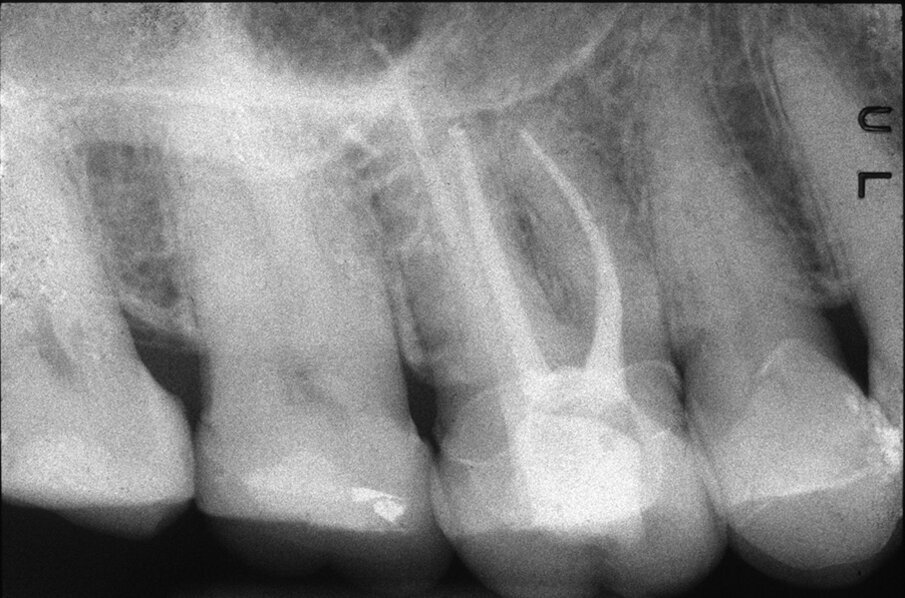

Le perforazioni del terzo medio avvengono nella maggior parte dei casi durante la preparazione della cavità d’accesso o, più spesso, durante le fasi di detersione e sagomatura o infine durante la preparazione dello spazio per un perno con l’utilizzo di frese tipo Largo, Peeso, Gates Glidden o simili (Figg. 2a-2f).